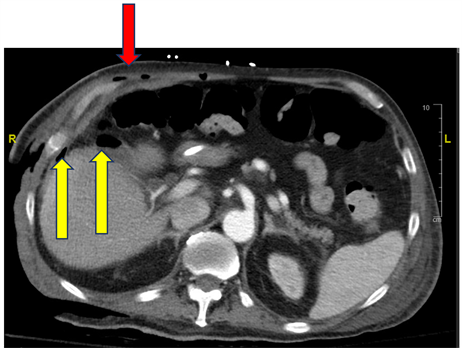

After arrival at MM’s medical center and upon physical examination, the patient was noted to have a large 40 × 50 centimeter soft tissue defect of the right anterolateral chest wall, abdomen, and flank down to muscle (Figure 1). Subsequent CT imaging revealed free air persisting in the subcutaneous and myofascial layers of the right anterior abdominal wall, intraabdominal free air, fluid within the fistulous tract from the gallbladder in the right upper quadrant, and a large right upper quadrant and flank soft tissue defect (Figure 2). The patient was immediately taken back to the operating room for additional soft tissue debridement of the involved areas of the right upper quadrant, chest wall, flank, and hip, extending to the right inguinal ligament. During the second and third surgical debridements multiple gallstones were removed from the right upper quadrant wound bed and confirmed with pathology. These findings, coupled with the history obtained from the referring facility, were consistent with necrotizing

Figure 2. Image of computerized axial tomography scan of the abdomen showing free air in muscles of the right upper quadrant abdominal wall and a large right lateral thoracoabdominal flank defect (red arrow), fluid with intrabdominal air along the fistulous tract from the still retained gallbladder (yellow arrows), and a large right flank soft tissue defect.